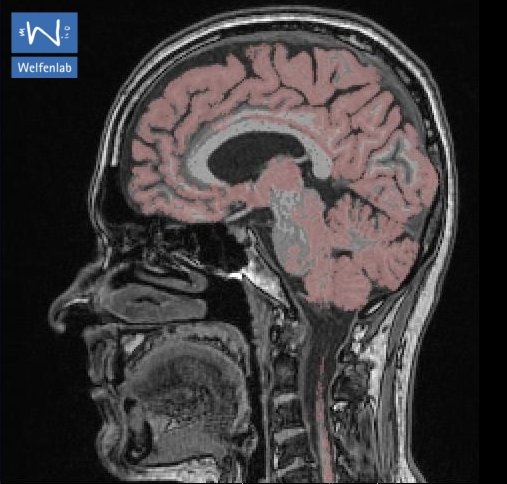

Ein besonders aktueller Schwerpunkt des Welfenlab ist die Visualisierung von Voxeldaten aus dem Bereich der Medizin. Unter einem Voxel kann man sich das dreidimensionale Gegenstück eines Pixels vorstellen. Während ein Pixel (bestehend aus einer x und y Koordinate zusammen mit einem Farbwert) einen Punkt auf einem Computermonitor beschreibt, besitzt ein Voxel zusätzlich eine z-Koordinate. Solche Voxeldaten werden u.a. durch verschiedene bildgebende Verfahren der Medizin gewonnen, z.B. durch Computertomographie (CT) oder Magnetresonanztomographie (MRT). Aus Sicht der Informatik stellt sich die Frage, wie solche Voxeldaten in einer für den Menschen verständlichen Art und Weise dargestellt werden können. Je nach Anwendung kommt es dabei entweder darauf an eine besonders schöne und leicht verständliche Visualisierung zu finden, oder eine möglichst schnelle, interaktive Darstellung bei der sich der Betrachter um das virtuelle Objekt herum oder sogar hindurch bewegen kann.

Zusammen mit dem Problem der Visualisierung tritt oft auch das Problem der Segmentierung auf. Unter diesem Begriff versteht man die Erzeugung von inhaltlich zusammenhängenden Regionen durch das Zusammenfassen von Pixeln oder Voxeln entsprechend einem bestimmten Homogenitätskriterium. Ein CT-Voxeldatensatz kann z.B. eine Aufnahme eines menschlichen Kopfes darstellen. Ein Teil dieser Aufnahme besteht aus Knochen, ein Teil des Knochens würde von einem Mediziner als "Unterkiefer" bezeichnet. Beides, sowohl "Knochen" als Oberbegriff als auch "Unterkiefer" als Teilmenge von "Knochen", bezeichnet man als Segment und die (manuelle oder automatische) Erzeugung eines solchen Segments als Segmentierung.

Beide Anwendungen, Visualisierung und Segmentierung werden am Welfenlab erforscht. Hierfür wurde mit dem Programm YaDiV ("Yet Another Dicom Viewer") eine eigene Software entwickelt, die DICOM Daten einlesen, anzeigen, segmentieren und registrieren kann. Die Evaluation der entwickelten Verfahren erfolgt durch Ärzte an der Medizinischen Hochschule Hannover MHH. Es ist geplant, YaDiV in den kommenden Wochen als OpenSource Software zu veröffentlichen. Mehr über YaDiV ...